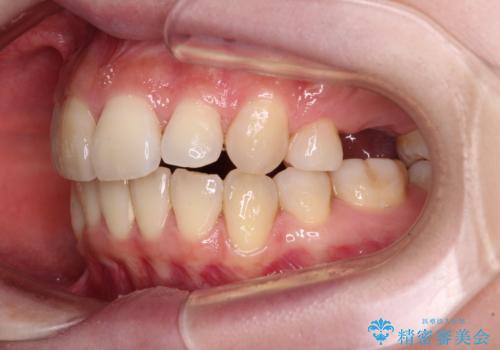

- 奥歯の欠損と、抜歯矯正の後戻りを気にして来院された患者様です。

上下前歯をワイヤー保定していましたが、強い舌の突出癖により上下ともにスペースができ、上下前歯は非接触になっていました。

また、上顎臼歯は虫歯により抜歯されてから放置されている状態でした。